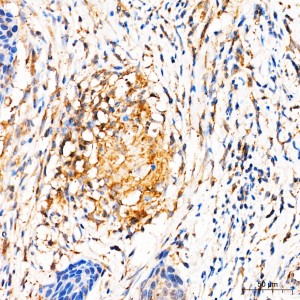

| Immunohistochemistry analysis of paraffin-embedded Human cervical squamous cell carcinoma tissue using [KD Validated] MRPL27 Rabbit pAb (A25221) at a dilution of 1:100 (40x lens). High pressure antigen retrieval was performed with 0.01 M citrate buffer (pH 6.0) prior to IHC staining. |